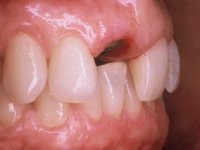

52-year-old female patient, non-smoker. He used an appointment with an implant already placed in the 1.1 site. It was provisionally rehabilitated with a composite resin crown adhered to the palatal surface of the adjacent teeth. This provisional had taken off several times in the last month, even in this first consultation it was taken off. We took advantage of this situation and verified that the “Tissue Level” implant had 2 to 3 mm of prosthetic space available. A deep bite and the inclination of the long axis of the implant posed a very difficult situation for the rehabilitator. If one chooses a abutment with a cemented crown, the height of the abutment would be minimal, with no retention or resistance. If a screwed solution is chosen, the screw access hole would emerge through the vestibular surface. It should be remembered that in 2006 the prosthetic solutions for this situation were limited to these options: 1- Screw-retained angled metal abutment for cemented crown 2 - Screw-retained angled metal abutment for transversally screw-retained crown 3 – Syn Octa metal abutment for screw-retained crown. A serious problem in this rehabilitation was guessed right from the start. The patient had a thick gingival phenotype and good oral hygiene.

After performing an impression of the implant and making the models, we tested several rehabilitative options with the help of the implant brand planning kit. None proved capable. In this sense and as a resource solution, an innovative solution was proposed. It was proposed to make a milled Zr abutment with an appropriate design to receive a veneer that would hide the screw access hole. The veneer itself had a ceramic-coated Zr infrastructure. The goal was to achieve retention and strength by screwing the abutment and aesthetically solve the case with the veneer.